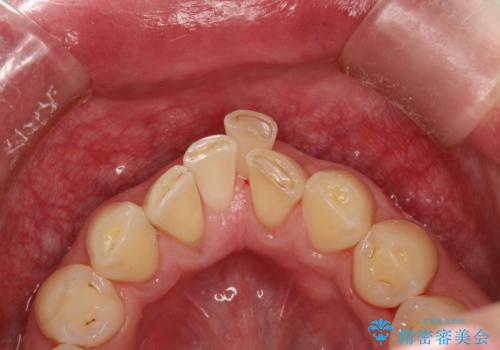

- 約3年ほど歯科医院での定期健診やクリーニングを受けてないとのことでした。全体的に歯石・着色などが付着していていたためPMTC60分コースを行いました。

分厚く歯石や着色が付着していると、汚れなのか虫歯なのかの判別がしづらい場合があります。しばらく定期健診やクリーニングを行っていない場合は、まずはしっかりと汚れを除去し、本来のご自身の歯の状態にすることで、より精密なお口の状態の診断が行えます。

PMTCによって、CRと、ご自身の歯の境目の着色などがしっかりと落とせて目立たなくなる場合と、PMTCによってしっかりとクリーニングを行うと、CR自体が古く劣化・変色などしていて目立ってくる場合があります。気になる際は詰め替えを行います。